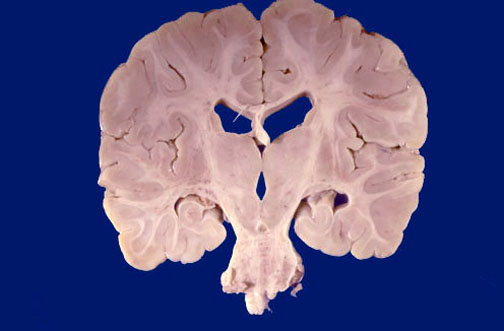

Identify the following regions of the normal brain in the image above: Pons - Thalamus - Fornix - Hippocampus - Third ventricle